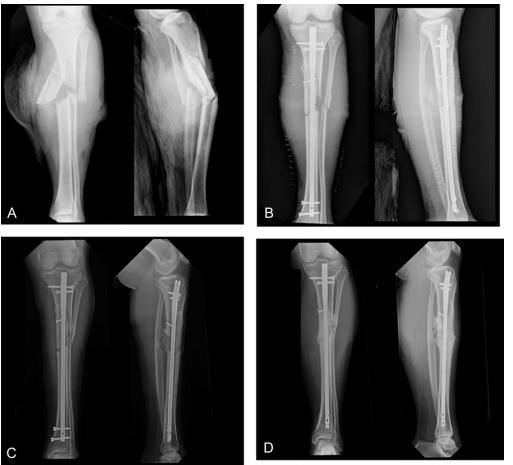

圖1 A、B 24歲男性,Ⅲ度脛骨開放性骨折;C術(shù)后161天拆除遠端螺釘行動力化治療骨折不愈合,RUST評分為5分;D術(shù)后334天骨折愈合,RUST評分10分

骨折延遲愈合或不愈合是脛骨骨折常見的并發(fā)癥,而且治療也較困難。文獻報道:髓內(nèi)釘治療脛骨骨折的不愈合率可達5%~17%(閉合性)和40%(開放性)。髓內(nèi)釘動力化和更換髓內(nèi)釘是常見的二次手術(shù)干預(yù)手段。動力化是指拆除髓內(nèi)釘近端或者遠端的靜態(tài)交鎖螺釘加強骨折端微動,從而促進骨折愈合(圖1)。更換髓內(nèi)釘包括移除髓內(nèi)釘、擴髓和植入更粗的髓內(nèi)釘。